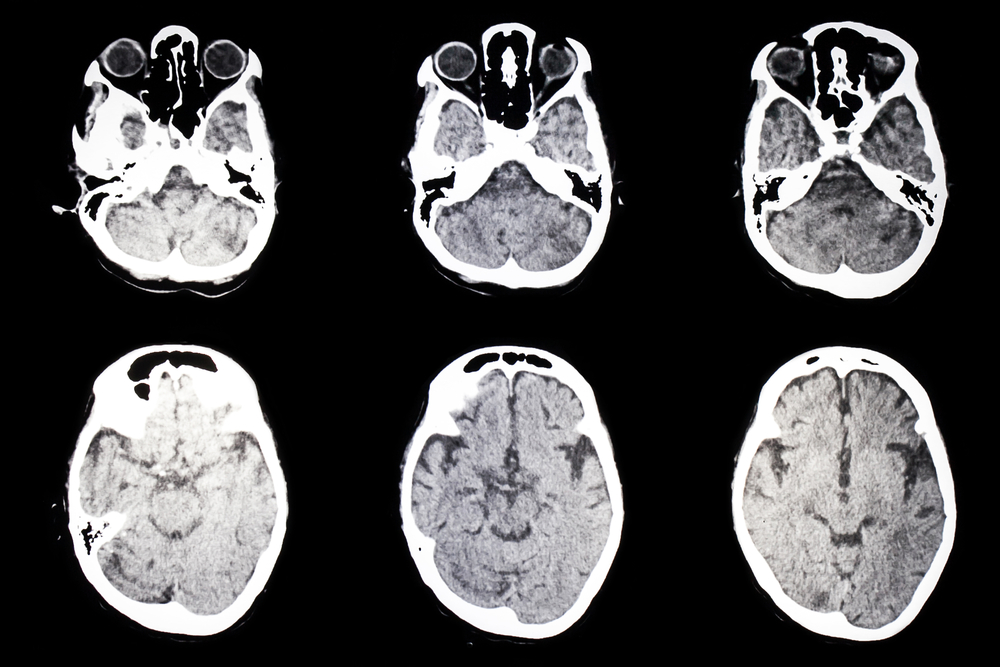

- Kompiuterinė tomografija ar rentgenas padeda aptikti būdingus smulkius kaulus kaukolėje, kurių atsiranda dėl jungiamojo audinio silpnumo.